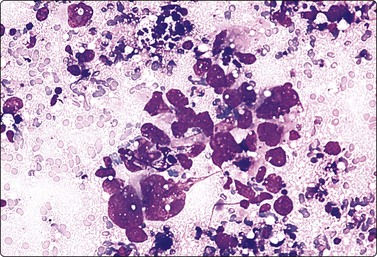

Prostatitis (Figs 13.3 and 13.4)4,36,37,39

image

Fig. 13.3 Prostatitis (acute)

Irregular epithelial sheet with mildly enlarged nuclei; background of neutrophils (DQ, HP).

Fig. 13.4 Prostatitis (granulomatous)

Many epithelioid histiocytes, multinucleated giant cell with phagocytosed secretion; many neutrophils (DQ, IP).

Mild epithelial atypia is acceptable in the presence of significant inflammation (Fig. 13.3). The distribution of cells in epithelial sheets may be less regular than normal and the cell membranes less distinct. Nuclei may be mildly enlarged and varying in size. Cytoplasmic granules are often absent, while degenerative changes such as cytoplasmic vacuolation are often seen. However, prominent nuclear enlargement and pleomorphism, nucleolar enlargement and chromatin abnormalities do not occur. There is little tendency to dissociation of epithelial sheets, and microacini are not seen. As inflammation may coexist with carcinoma, epithelial atypia must be carefully evaluated. We require the presence of epithelial sheets encrusted with polymorphonuclears to arrive at the diagnosis of acute prostatitis.

Granulomatous prostatitis (Fig. 13.4)36,37,39 remains a diagnostic dilemma since both clinical and cytological findings may mimic carcinoma. The cytological diagnosis of non-specific granulomatous prostatitis or tuberculous prostatitis, respectively, is based on the presence of epithelioid granulomas or obvious caseous necrosis. Nuclear overlapping, anisonucleosis, occasionally striking atypia, naked nuclei and some acinar formation may result in a false-positive diagnosis. Epithelial atypical cells in granulomatous prostatitis show a typical basophilia in DQ-stained smears; this basophilia is not seen in prostate carcinoma cells.